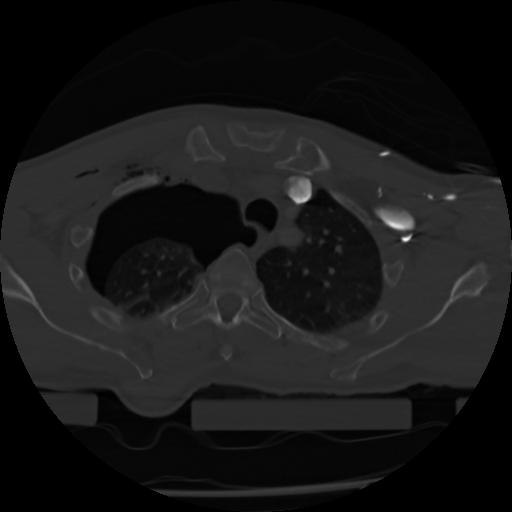

21 ANGIO,CE,Axial,3.0,ANGIO,,